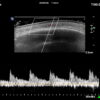

Study the first image to recognize the different layers. If you are sure about the layers, swipe to the second image to view the answer (if applicable).